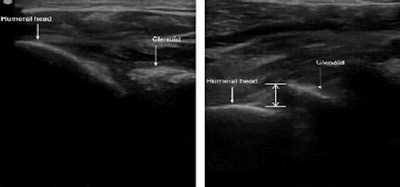

A posterior approach was used in the study. All images courtesy of Alex Trinh.Acute shoulder dislocations are commonly seen in the ED and affect 1.7% of the population in the U.S. Of the dislocations, 97% are anterior in nature, meaning that the humeral head is dislodged anteriorly to the glenoid rim, Trinh said.

After an ultrasound image of the humeral head and glenoid rim was obtained, the glenohumeral separation distance was determined. If ultrasound shows that humeral head placement is posterior to the glenoid rim, then there is no dislocation, according to Trinh.

Conversely, "if the humeral head placement is anterior to the glenoid rim, the shoulder is likely anteriorly dislocated," he said.

Ultrasound scans of normal (left) and anteriorly dislocated shoulder (right). The humeral head is located posterior to the glenoid rim in the normal shoulder. In the anterior dislocation, the humeral head is anterior to the glenoid rim.